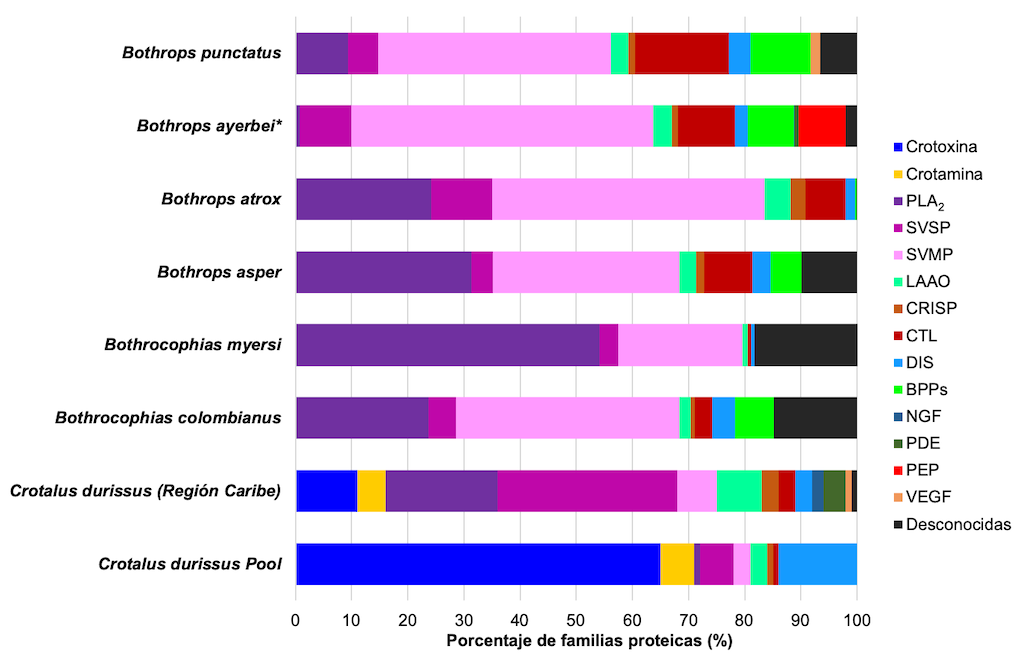

La variabilidad del veneno se produce debido a las trayectorias evolutivas de las serpientes venenosas, así como a la especialización de algunas de sus toxinas. Por ejemplo, los venenos tanto de las familias Elapidae y Viperidae están dominados por dos o tres familias de proteínas: fosfolipasas A2 (PLA2) y toxina de tres dedos (3FTx) para los elápidos, y metaloproteasas (SVMP), PLA2 y serino proteasas (SVSP) para los vipéridos. En promedio, estas familias de proteínas constituyen el 83% y el 67% del proteoma del veneno de elápidos y víboras, respectivamente [24].

Los venenos de serpientes de la familia Elapidae son principalmente neurotóxicos, mientras que los de la familia Viperidae inducen coagulopatías, hemorragias y daños tisulares locales [25,26]. Esto se debe a la prevalencia de las proteínas 3FTx y PLA2 en el veneno de elápidos que pueden causar debilidad similar a la miastenia gravis [27]. Esta debilidad puede afectar a cualquier músculo; y si el bloqueo neuromuscular afecta a los músculos de la respiración, puede provocar la muerte [26,27]. Por otro lado, el veneno de vipéridos tiene efectos principalmente hemotóxicos y miotóxicos. Los agentes identificados en el veneno de las víboras incluyen proteinasas similares a la trombina que provocan coagulopatía [28], hialuronidasas que alteran las matrices extracelulares, fosfolipasas A2 que causan inflamación local y dolor [29], y metaloproteasas que contribuyen a la hemorragia [30,31]. El resultado es una destrucción local del tejido empeorada por el efecto coagulopático [26].

Existe una amplia variación en los perfiles de veneno entre especies dentro del mismo género [32–34]. Por ejemplo, los perfiles proteómicos de los venenos de dos especies de vipéridos del género Bothriechis, B. lateralis y B. schlegelli, muestran que los venenos de estas dos especies contienen péptidos potenciadores de bradicinina (BPP) y proteínas PLA2, serinoproteasas, L-aminoácido oxidasas (LAAO), proteínas secretoras ricas en cisteína (CRISP) y metaloproteasas dependientes de Zn2+ (SVMP). Sin embargo, cada especie tiene una abundancia relativa diferente de cada familia de proteínas. Además, cada veneno contiene componentes distintos. Por ejemplo, B. lateralis contiene factor de crecimiento endotelial vascular (VEGF) y moléculas similares a lectina de tipo C, mientras que B. schlegelii tiene inhibidores de proteasa de tipo Kasal [35].

Las proteínas del veneno de ambas especies de Bothriechis son similares en menos del 10%, lo que indica una divergencia significativa en la composición del veneno. A pesar de que ambas especies se adaptan a hábitos arbóreos, las características bioquímicas de su veneno probablemente estén relacionadas con las características de las presas que consumen [32,35]. La composición de los venenos puede proporcionar pistas para racionalizar los diversos signos de envenenamiento causados por B. schlegelii y B. lateralis [35].

También existe variación en el perfil del veneno de serpiente entre individuos de la misma especie, encontrándose diferencias intraespecíficas por ubicación geográfica [28,36,37]. Por ejemplo, se analizó a nivel de subespecie la composición y el perfil toxicológico del veneno de la serpiente cascabel Crotalus simus en México. Los venenos de la subespecie C. s. simus, C. s. culminatus y C. s. tzabcan difieren en la expresión del complejo neurotóxico «crotoxina». Crotalus s. simus tiene la mayor concentración de crotoxina seguida de C. s. tzabcan, mientras que el veneno de C. s. culminatus está casi desprovisto de este PLA2 neurotóxico. El análisis proteómico se correlaciona estrechamente con los perfiles toxicológicos. Por ejemplo, C. s. simus contiene altas cantidades de crotoxina y serinoproteasas, mientras que el veneno C. s. culminatus tiene mayores cantidades de metaloproteasas y crotamina. Esto sugiere que la variación geográfica en la composición del veneno puede reflejar la selección natural para alimentarse de presas locales [38]. La creciente aparición de crotamina en poblaciones de Crotalus es razón suficiente para advertir sobre la necesidad de desarrollar un antiofídico que pueda neutralizar esta toxina [36].